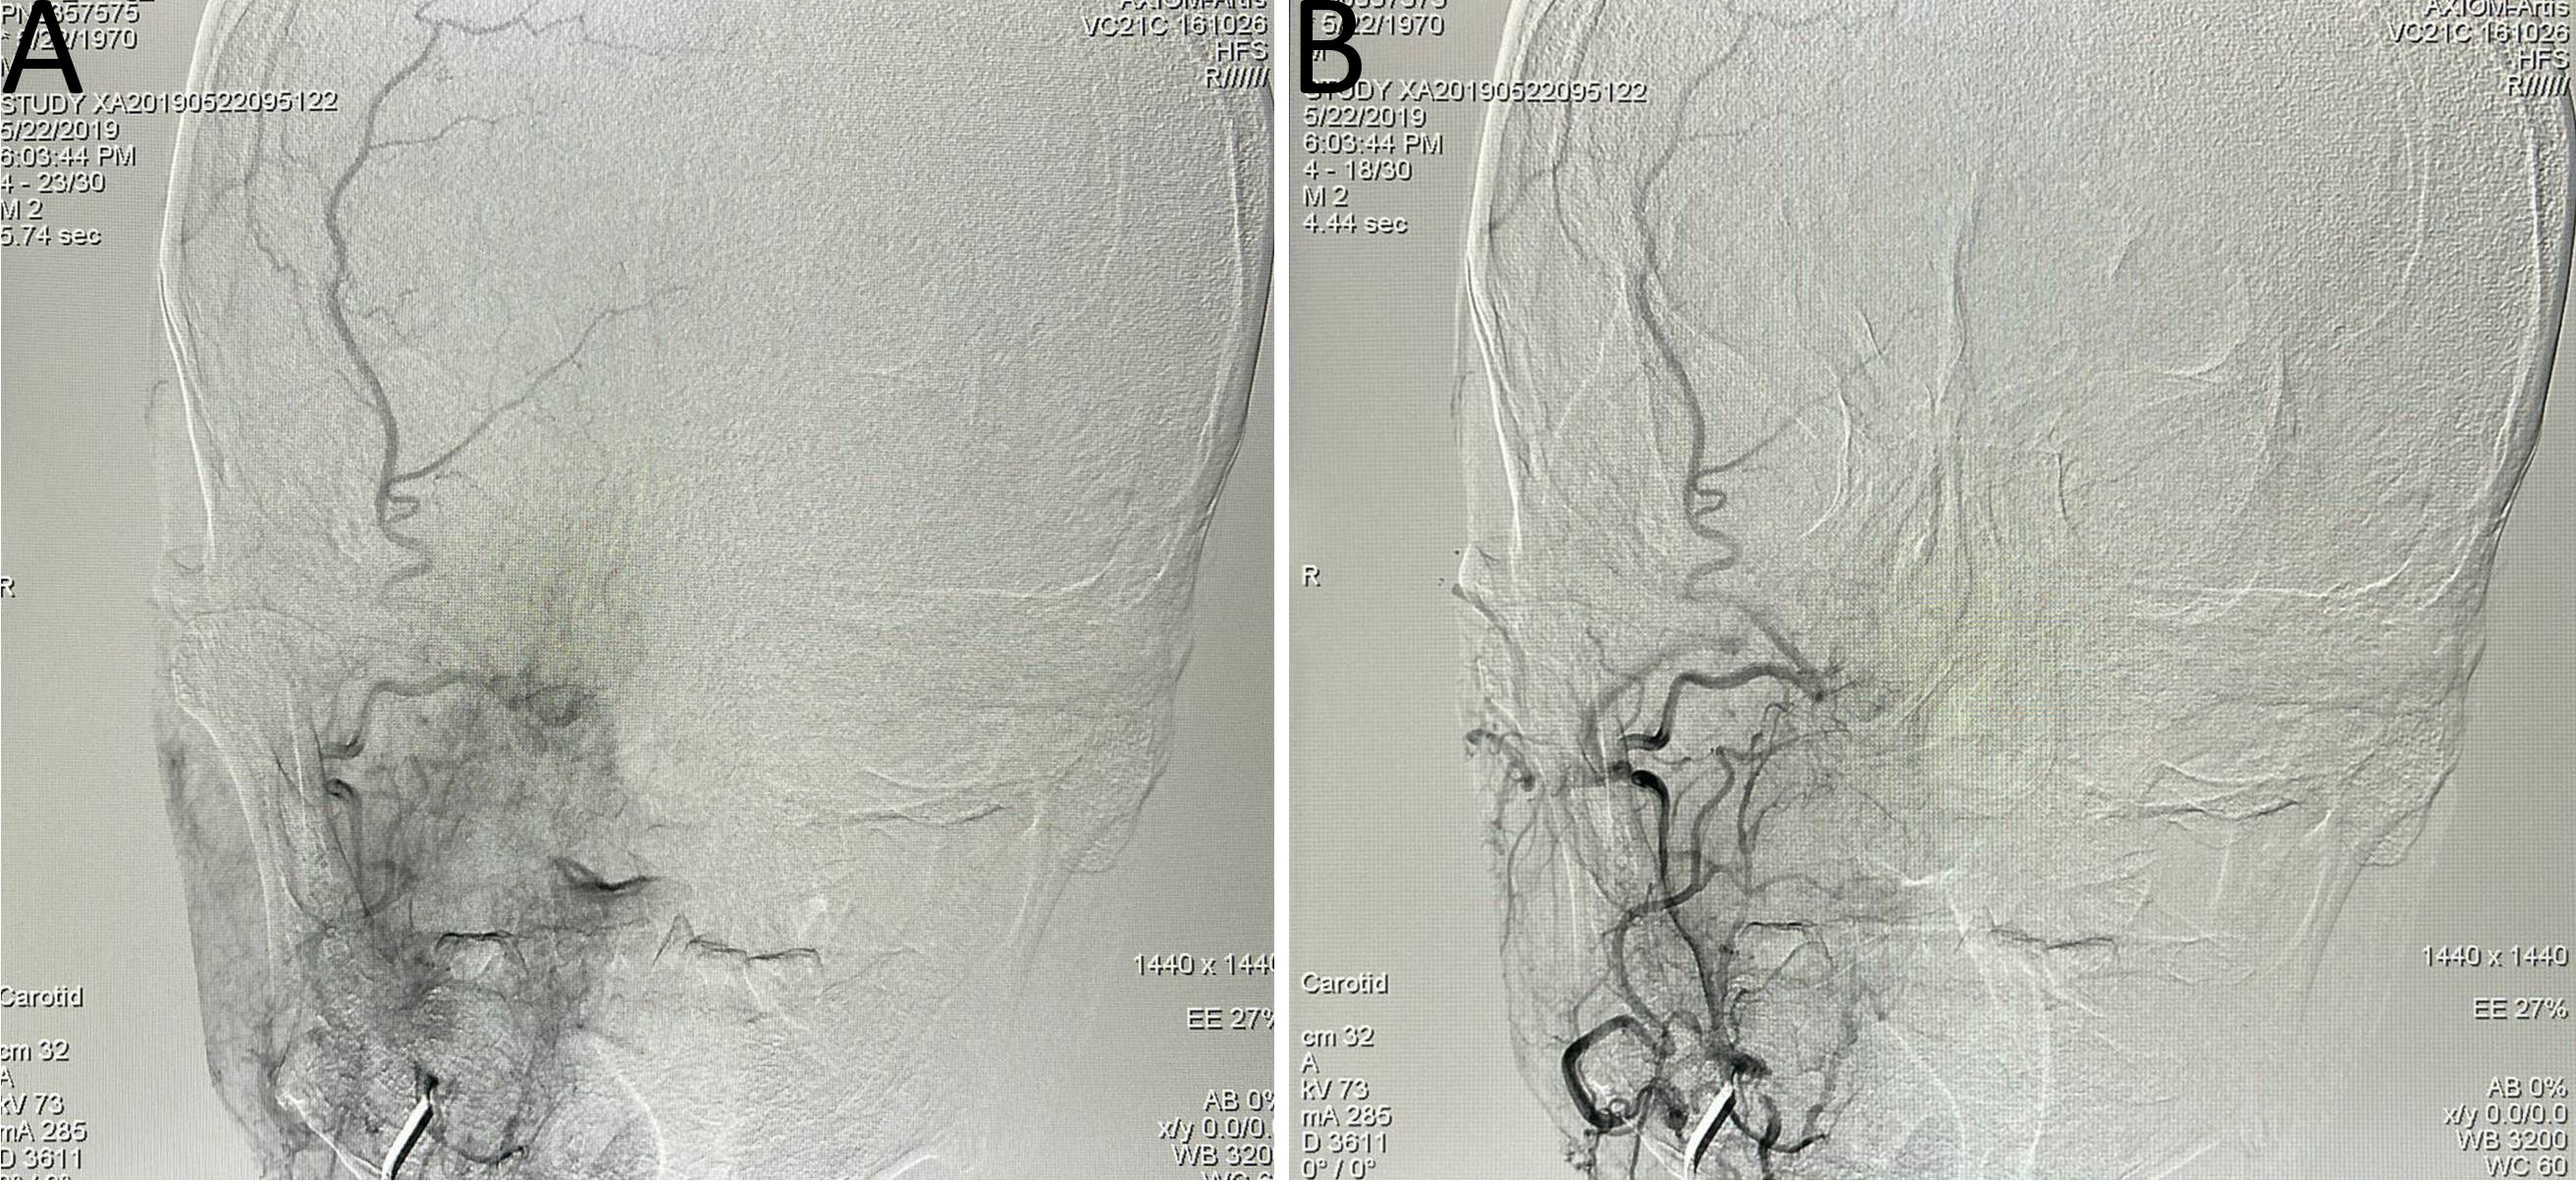

Figure 1

Balloon occlusion test (BOT) procedure steps. (A) Following balloon occlusion of the right internal carotid artery, insufficient compensatory blood flow was observed through the anterior communicating artery. (B) Balloon occlusion of the right internal carotid artery demonstrated limited compensatory blood flow through the posterior communicating artery. (C, D) Pseudoaneurysm identified at the ruptured segment of the right internal carotid artery (prior to stent implantation). (E) Intraoperative image during covered stent placement at the ruptured segment of the right internal carotid artery. (F) Post-stent implantation angiography showed unobstructed blood flow through the treated segment. (G, H) Computed tomography angiography (CTA) confirmed appropriate positioning of the covered stent.

Upon admission, routine blood analysis indicated a hemoglobin level of 11.2 g/dL, raising suspicion of ICA rupture-associated hemorrhage. An urgent DSA examination confirmed the presence of a pseudoaneurysm in the petrous segment of the right ICA, with tumor-associated stenosis of the involved arterial segment. A subsequent BOT yielded a positive result (refer to Figures 3A, B).

Figure 3

(A, B) Digital subtraction angiography (DSA) indicated a pseudoaneurysm in the petrous segment of the right internal carotid artery, with tumor-related narrowing; the balloon occlusion test was positive. (C, D) Post–covered stent implantation DSA showed disappearance of the pseudoaneurysm, restoration of normal vascular morphology, and adequate perfusion of intracranial branch arteries. (E, F) Vascular reconstruction after stent implantation confirmed favorable vascular morphology and intracranial branch perfusion. (G, H) Follow-up DSA indicated recurrence of a small aneurysm distal to the stent in the petrous segment (C2) of the right internal carotid artery. (I) Vascular reconstruction angiography at three months post-stent implantation demonstrated a dissecting aneurysm.

Covered stent implantation was performed at the petrous segment of the right ICA, leading to the disappearance of the pseudoaneurysm. Post-procedural imaging demonstrated satisfactory vascular morphology and adequate perfusion of all intracranial branch arteries (refer to Figures 3C–F). Immunotherapy with sintilimab, a programmed cell death protein 1 (PD-1) immune checkpoint inhibitor, was administered every three weeks.

However, severe nasal bleeding recurred three months later. DSA and vascular reconstruction revealed septal luminal irregularities in the left carotid artery, consistent with a dissecting aneurysm (refer to Figures 3G–I).